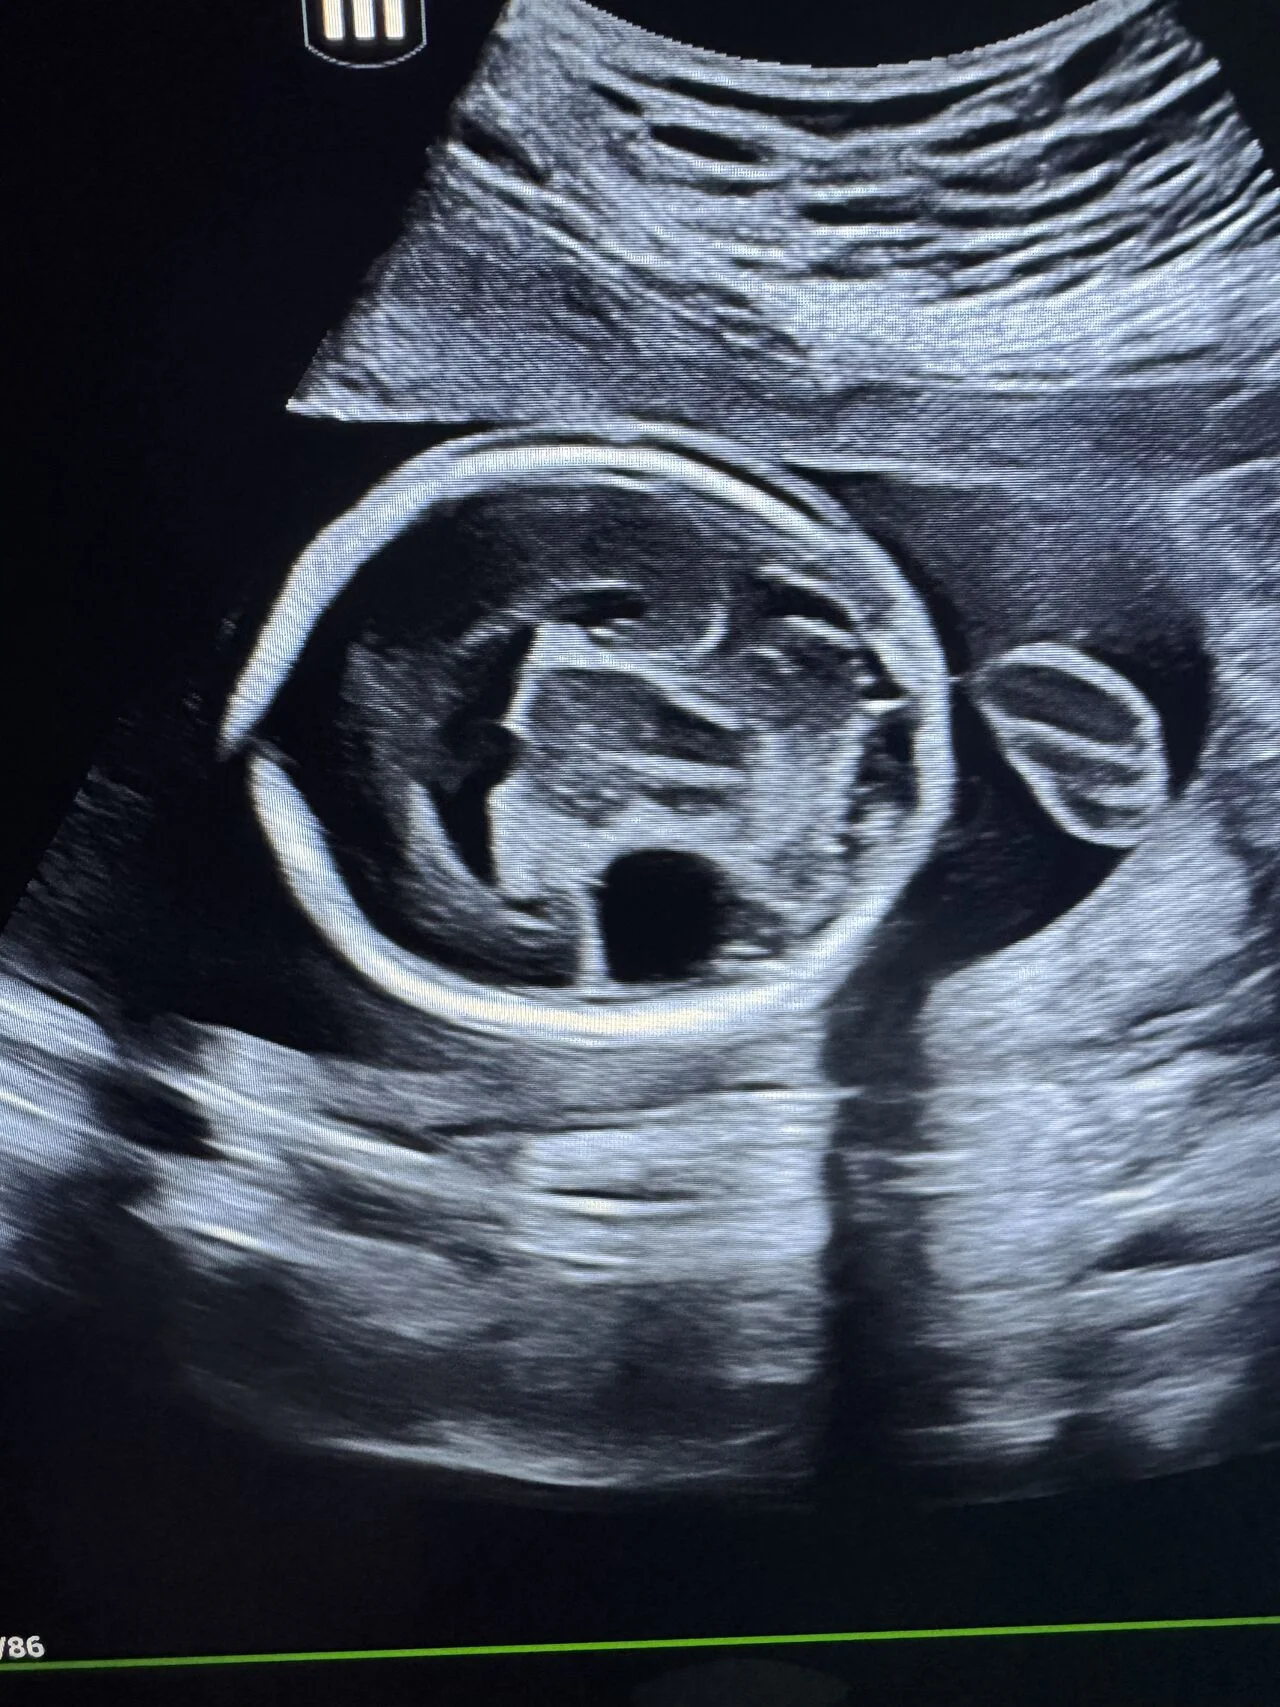

“Fetal Anomaly Case | Semilobar Holoprosencephaly

A prenatal ultrasound case demonstrating features of semilobar holoprosencephaly.

Key neurosonographic findings:

- Single midline ventricular cavity

- Fused thalami

- Partial absence of interhemispheric fissure

- Absent cavum septum pellucidum

3D imaging revealed associated midline facial abnormalities.

An associated ventricular septal defect (VSD) was also identified.

Holoprosencephaly represents a spectrum of forebrain malformations with strong association to chromosomal abnormalities, particularly trisomy 13.

Genetic counseling and further evaluation are essential in such cases.

This case highlights the importance of systematic fetal neurosonography and correlation with extracranial anomalies.”